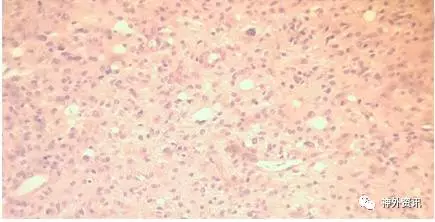

1994年,44岁的男性患者,因剧烈头痛伴左臂无力1月余就诊;头颅MRI成像显示右额后深部肿瘤(图1A),施行手术切除肿瘤。手术过程较为顺利,肿瘤标本的病理学诊断为多形性胶质母细胞瘤。术后患者接受全脑放疗和化疗。随访3周时发现左上肢无力症状消失。3月时头颅CT复查未见肿瘤复发。以后定期复查头颅MRI,均提示肿瘤未复发(图1B),直至2016年7月头颅MRI复查仍未见复发,而患者术后已存活22年。请3位神经病理学家复读病理组织切片,证实为典型的恶性胶质瘤。

图1. 患者术前与术后的头颅磁共振成像比较。A. 术前MRI显示肿瘤位于右额叶后部深处,增强扫描时呈强化灶,内有坏死区,周围脑组织水肿;B. 术后MRI复查未见肿瘤复发。

图2. 病理学检查结果。上图:HE染色示伴有微囊性变的胶质瘤多细胞簇,核仁明显,核有高度异型性。下图:A.GFAP免疫反应性强烈;B.免疫染色显示Ki-67增殖指数高。